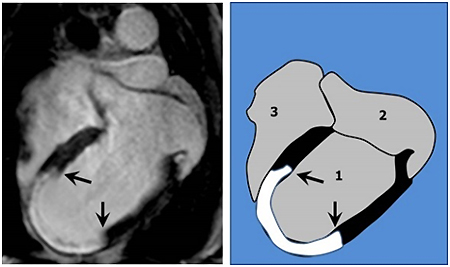

Izquierda: resonancia magnética del corazón de un paciente tras sufrir un infarto. Derecha: representación explicativa. 1: ventrículo izquierdo, 2: aurícula izquierda, 3: ventrículo derecho. El músculo principal del corazón es el del ventrículo izquierdo (representado en negro). Un músculo sano debe aparecer negro en la resonancia. Tras un infarto, la parte de corazón que queda necrosada aparece en blanco tras la administración de un contraste